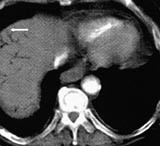

Ved ankomst i sykehuset var han kaldsvettende, forvirret og klaget over smerter i venstre bein. Han hadde ikke buksmerter. Han hadde puls 190/min, uregelmessig, systolisk blodtrykk 210 mm Hg og normal kroppstemperatur. Buken var lett utspilt, uten ømhet eller andre tegn på peritonitt. Venstre bein hadde nedsatt sirkulasjon. EKG viste raskt atrieflimmer. Pasienten var kritisk syk. Behandling av hans raske atrieflimmer med verapamil og metoprolol bedret ikke situasjonen. Blodprøver viste Hb 19,0 g/100 ml (jf. 17,4 g/100 ml to måneder tidligere), leukocytter 21,7 × 10 9 /l, trombocytter 226 × 10 9 /l, CRP 138 mg/l, natrium 141 mmol/l, kalium 3,3 mmol/l, albumin 42,3 g/l, kreatinin 140 µ mol/l, bilirubin 25 µ mol/l, ASAT 262 U/l, ALAT 139 U/l, CK 227 U/l, amylase 139 U/l. CT abdomen viste en normalt kalibrert aorta med tromber i venstre a. iliaca og i a. mesenterica superior. Det forelå en fyllingsdefekt nær avgangen av truncus coeliacus, samt fravær av kontrastfylling i coeliacusgebetet. Forgrening av luft var synlig i leveren (fig 1), helt ut til leverkapselen (fig 2). Luft var også synlig i den ekstrahepatiske del av portvenen, samt i miltvenen og i mesenteriale vener (fig 3). Det forelå ingen utvidelse av magesekken, og heller ingen intramural luft. Vi mistenkte en vaskulær katastrofe i buken. På vei til operasjonsstuen mistet pasienten bevisstheten og døde.

Det er alminnelig anerkjent at luft som forgrener seg lenger distalt enn 2 cm fra leverkapselen, gjengir et luftportogram, snarere enn et luftkolangiogram (1 – 3). Det sistnevnte er et hyppigere og mindre illevarslende funn. Luftportogram er også kjent i engelskspråklig litteratur som ”hepatic portal venous gas”, forkortet HPVG. Luftportogram er beskrevet i forløpet av en rekke ulike abdominale katastrofer, oftest i forbindelse med tarmnekrose (4, 5), og er med få unntakelser et varsel om elendig prognose (1). Tidligere ble dette tegnet alene sett på som tilstrekkelig indikasjon for øyeblikkelig laparotomi (1, 6). I den senere tid er det publisert enkelte rapporter om mindre kritiske tilstander som også har ført til danning av luft i portvenesystemet, spesielt inflammatoriske tarmsykdommer, både spontant og etter endoskopi/røntgen colon (7 – 9), tarmparalyse (10), dilatasjon av ventrikkelen (11, 12), divertikulitt med abscessdanning (2, 13 – 16) og tarmobstruksjon (17). Det kan også være et resultat av stumpt eller penetrerende traume (18 – 20). Skader av mucosa og distensjon av ventrikkel/tarm antas å være disponerende faktorer. Tilstander i ventrikkelen er sjelden årsak til luft i portvenesystemet. Blant disse er lokale infeksjoner og gastrisk emfysem. Sistnevnte beskriver tilstander der luft er presset inn i ventrikkelveggen på grunn av intraluminal dilatasjon, oftest iatrogent, obstruktivt eller traumatisk betinget (21, 22). Prognosen er utmerket.